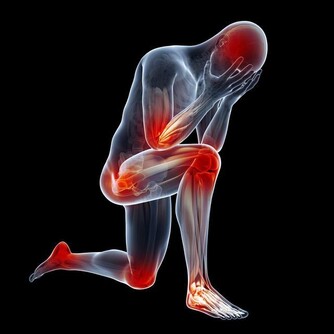

④四肢血管堵塞,或發生動脈硬化,可能很容易出現下肢動脈硬化閉塞症,下肢會發黑、疼痛,還會出現跛腳的症狀。